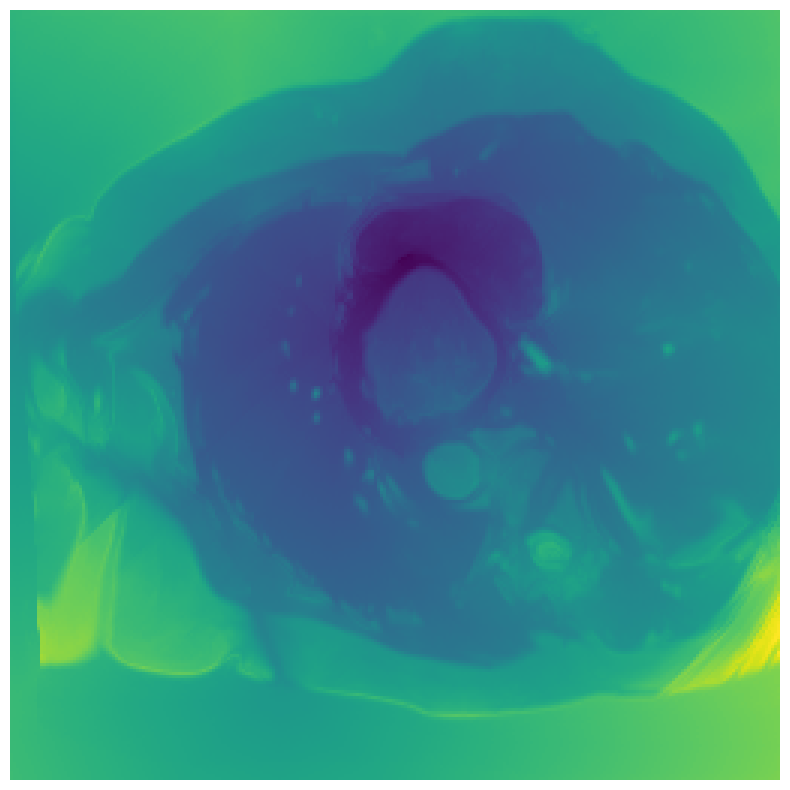

Generally, given an exact, full annotation of an object, such a Euclidean signed distance map encodes also information on the shape of an object. But when using a weak ground truth , where and , inferring a correct extent and shape of the objects is nontrivial. As shown in 1(b), Euclidean distance calculated from a point label source grows radially, regardless of the actual shape of the object, and thus makes little sense from an information point of view. Under the assumption of intra-object homogeneity and inter-object contrast (w.r.t intensities), this problem can be circumvented to a degree by using a distance function that takes also intensity values into account. An example of a commonly used distance measure with an intensity component is the Geodesic distance ([34]). Let denote a path between , with and being neighbors under a chosen adjacency relation. Reusing the notation from before, a Geodesic distance map from the boundary of the ground truth class , , can be defined as

Both the Intensity and the Minimum barrier distance are defined exclusively on the image intensity space. However, from the examples of distance map in 1(d), we can notice that the values still increase somewhat radially from the annotation. This behaviour is similar to the one of the Geodesic distance in 1(c) (which actually includes the spatial proximity in its definition), and is due to the summing operator in the general Geodesic distance definition in Equation 3. While the intensities of two neighboring pixels on a path may be the same, that will rarely be the case in real life, noise riddled images. This makes the Intensity distance function approximately monotonically increasing with increasing length of the path (in space), even on paths where the intensity is mildly fluctuating (e.g. consider a path with even pixels intensity value of and odd pixels intensity value of ). One could thus argue that such a definition of a distance, despite being based exclusively on intensities, is still capable of loosely encoding the spatial distance information.

On the other hand, while we can see that the MBD based maps are similar to Geodesic and Intensity ones (1(e)) with respect to the object shape recovery, they have a less pronounced and smooth increase in the values outward from the source point.

In contrast to Euclidean distance, the Geodesic, Intensity and Minimum barrier distance maps all encode contrast sensitivity and preserve the object structures by harnessing the intensity information of the underlying image. This holds even when calculated from point sources. In practice, using such maps for network training could mean a lower penalty for false positives that occur farther from the point annotation but are close to it in intensity. Thus still enabling the propagation of a sort of shape information (as it can be inferred from the raw image intensities).

We normalize the volumes and resize the slices to pixels. As the official dataset comes with full annotations, we create a synthetic point ground truth. This is done by first randomly choosing the centers of the point annotations within the class masks, followed by filling an ellipse with axes lengths of and (in pixels) around each center. The intersections of these elliptic discs with the underlying full annotations are then used as our point ground truth. See Figure 2 for an example of the created weak annotation mask. The point annotations are created for every slice, one for each foreground object present in the slice.

In Figure 6 we provide qualitative results on a number of randomly chosen test set slices. Upon visual inspection, we can observe that training with the intensity-aware distances (particularly with and ) follows the image gradients better and is better at recovering the underlying shape than the Euclidean version. The CRF-loss seems to recover the shape of the myocardium and left ventricle to some extent, but fails entirely on the right ventricle.